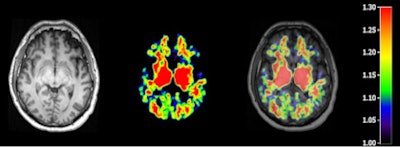

T1-weighted MR (left panel), C-11 PiB PET (middle panel), and fused image (right panel) from a patient 48 hours following severe traumatic brain injury. Image courtesy of Dr. David K. Menon, PhD.At the same time, PET imaging techniques with several carbon-11-labeled and F-18-labeled ligands to view beta amyloid in the brain have been developed and used in Alzheimer's research. Pittsburgh Compound B, for example, is one such validated marker for cerebral amyloid deposits.

To help segment areas of the brain into tissue classes and delineate anatomical regions of interest, participants also underwent an anatomical 3-tesla MRI scan using a Tim-Trio scanner (Siemens Healthcare).

The researchers also measured the PiB distribution volume ratio and standardized uptake value (SUV) ratio in the PET images, specifically looking at cortical gray matter, white matter, and multiple cortical and white-matter regions of interest, as well as striatal and thalamic regions of interest. Those regions of the brain are associated with executive function and memory and are likely to show early signs of Alzheimer's disease.